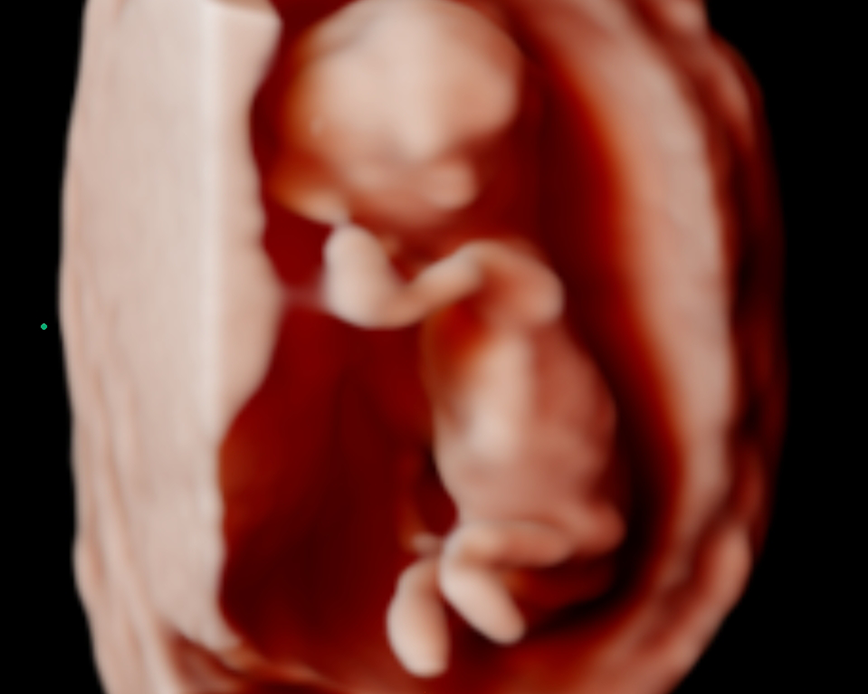

Con nuestra tecnología 5D y 6D de alta resolución, podrás ver la carita, las manos, los pies, la columna y el sexo de tu bebé con imágenes de alta calidad. Además, podrás apreciar los gestos de tu bebé en tiempo real. Esta ecografía también nos ayuda a detectar las malformaciones congénitas que pudiera tener el feto.